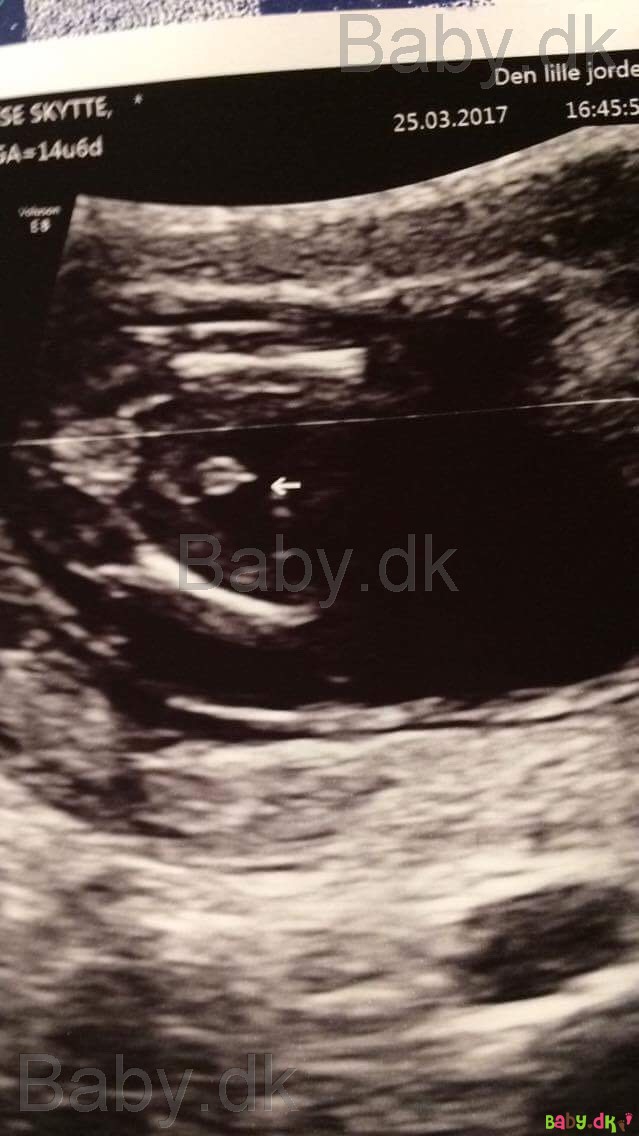

Jeg blev rykket to dage frem i min termin til Nf scanning

De rykkede os min 2 dage til min nf så jeg har den 9 april istedet for den 7

spændende med kønsscanningen, overvejede det men kæresters syndes det er for mange penge af bruge når vi skal til scanning om små 4 uger